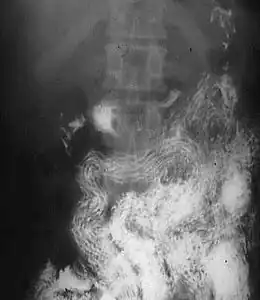

Ascaridiose

Causée par Ascaris lumbricoïdes, un grand nématode rosé de 15 à 25 cm de long. L'infection peut être asymptomatique en cas de charge parasitaire faible. On retrouve exceptionnellement un syndrome de Löffler lors de la phase de migration larvaire. À la phase d'infestation intestinale, on retrouve quelques troubles digestifs non spécifiques. Les complications sont exceptionnelles. Les vers adultes peuvent sortir spontanément par la bouche, le nez ou l'anus. Le diagnostic peut être fait à l'examen des selles qui retrouve des œufs ovales. Le traitement repose sur les antihelminthiques intestinaux et notamment l'ivermectine.